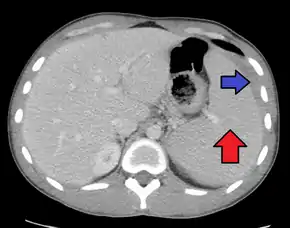

Spleen enlargement is common in the second and third weeks, although this may not be apparent on physical examination. Rarely the spleen may rupture.[24] There may also be some enlargement of the liver.[22] Jaundice occurs only occasionally.[14][25]

Splenomegaly is a common symptom of infectious mononucleosis and health care providers may consider using abdominal ultrasonography to get insight into the enlargement of a person's spleen.[58] However, because spleen size varies greatly, ultrasonography is not a valid technique for assessing spleen enlargement and should not be used in typical circumstances or to make routine decisions about fitness for playing sports.[58]